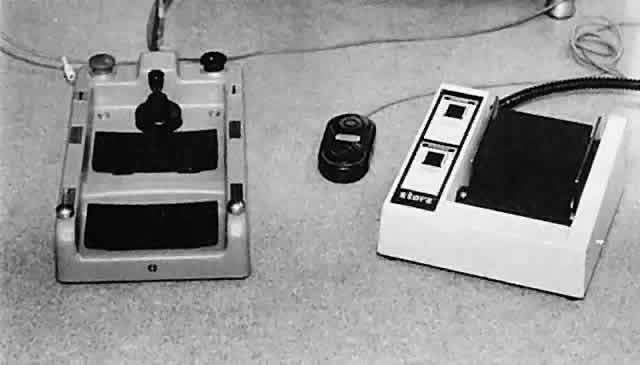

HEMOSTASIS Hemostasis commonly is achieved by applying heat to tissue, which causes

coagulation. Cauterization may range from interruption of blood flow

of vessels to blanching of tissue, gross charring of tissue, and in extreme

cases, tissue contraction (Fig. 30). The only way to monitor the application of heat is by anticipating the

power needs and visualizing the results. Care in this area is key to

controlling the delivery of heat to tissues. Excessive heat may cause

tissue contraction and wound deformation. Heat is generated in tissues

by monopolar or bipolar diathermy. Monopolar miniature diathermy probes

are used for intraocular coagulation. Bipolar diathermy is used to

generate heat in tissues either by grasping the tissue to be coagulated

or by applying indirect bipolar diathermy through a liquid film. With

either method of delivery, the bipolar diathermy unit requires that

the tissue to be coagulated remain between the probes of the diathermy

unit. Therefore, the forceps tips of the diathermy unit must be closely

approximated but not touching. As soon as the bleeding vessel coagulates, the

foot pedal should be released to limit tissue contraction. Changing

the voltage while keeping the space between the diathermy probes

constant controls the diathermy. In this way, increased voltage

results in increased energy delivery; however, in effect, keeping the

voltage constant and bringing the probes closer together increases the

energy delivered to the tissue. Delivery of excessive heat or energy

causes significant tissue shrinkage that may result in wound deformation.  Fig. 30. Hemostasis achieved through cauterization provides for interruption of

blood flow in vessels. The application of heat is monitored through visualizing

results. Excessive tissue shrinkage should be avoided. Coagulation

is visualized by the interruption of blood flow through the vessel. Fig. 30. Hemostasis achieved through cauterization provides for interruption of

blood flow in vessels. The application of heat is monitored through visualizing

results. Excessive tissue shrinkage should be avoided. Coagulation

is visualized by the interruption of blood flow through the vessel.

|